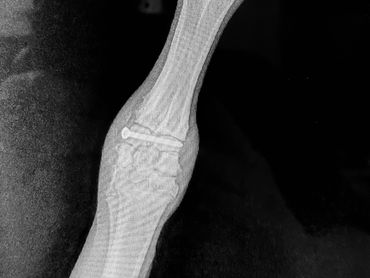

Remington had an unfortunate run-in with a hayfeeder when he was 9 months old and managed to dislocate a tiny bone in his knee that required surgery and the placement of a screw. He was confined to a very small area for about a month to keep him from moving around much, followed with moving into a little bigger stall in the buck pen – again because goats do dumb things and he needed time to heal. Despite physical therapy twice a day, he does have some significant stiffness in that leg making his gait a little wonky. Please give him a little grace because getting him to stand still (he wants to be in the middle of everything) and set him up is really difficult. And he’s black, making photos even harder.